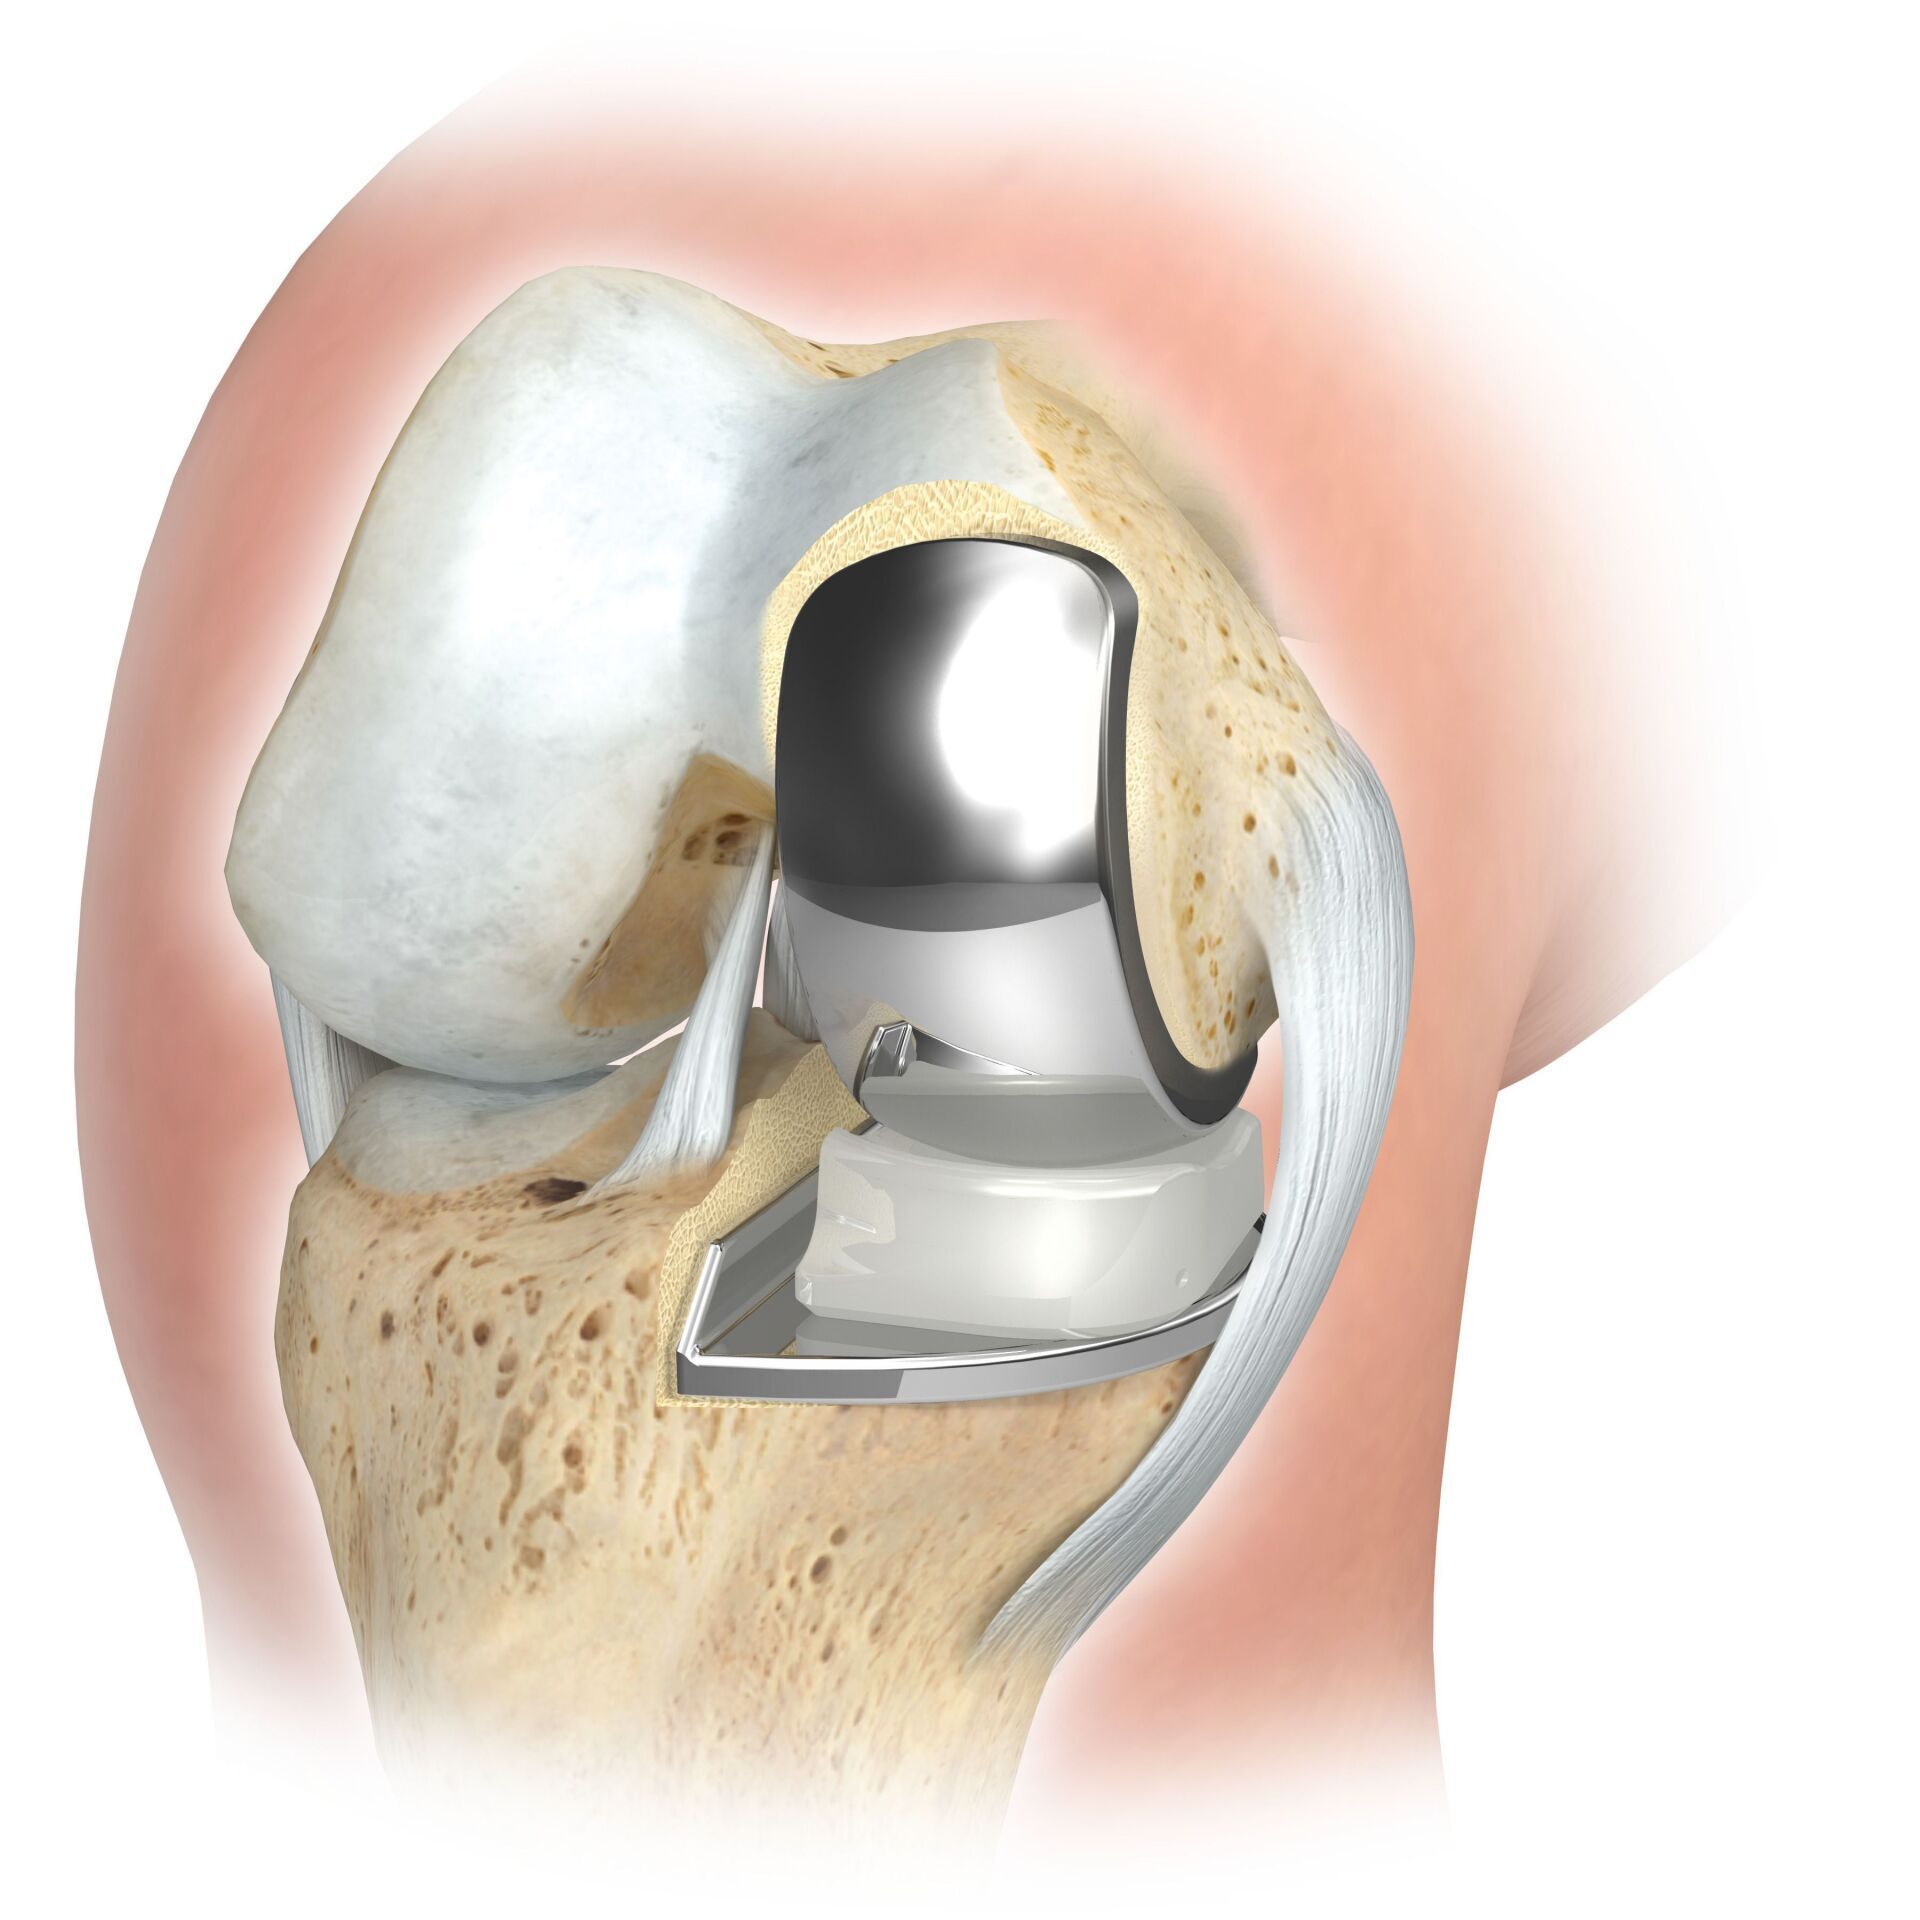

KNEE REPLACEMENT (ARTIFICIAL KNEE JOINT)

The artificial knee joint replaces the cartilage surface destroyed by arthrosis. The underlying bone on the thigh and tibial head remains intact. Some people compare a modern artificial knee joint to a crown on a tooth; the exact term is the so-called bicondylar surface replacement. Between the new surfaces on the thigh and lower leg is the so-called inlay made of a specially hardened white plastic, which can be seen in the X-ray image as the gap between the metal parts.